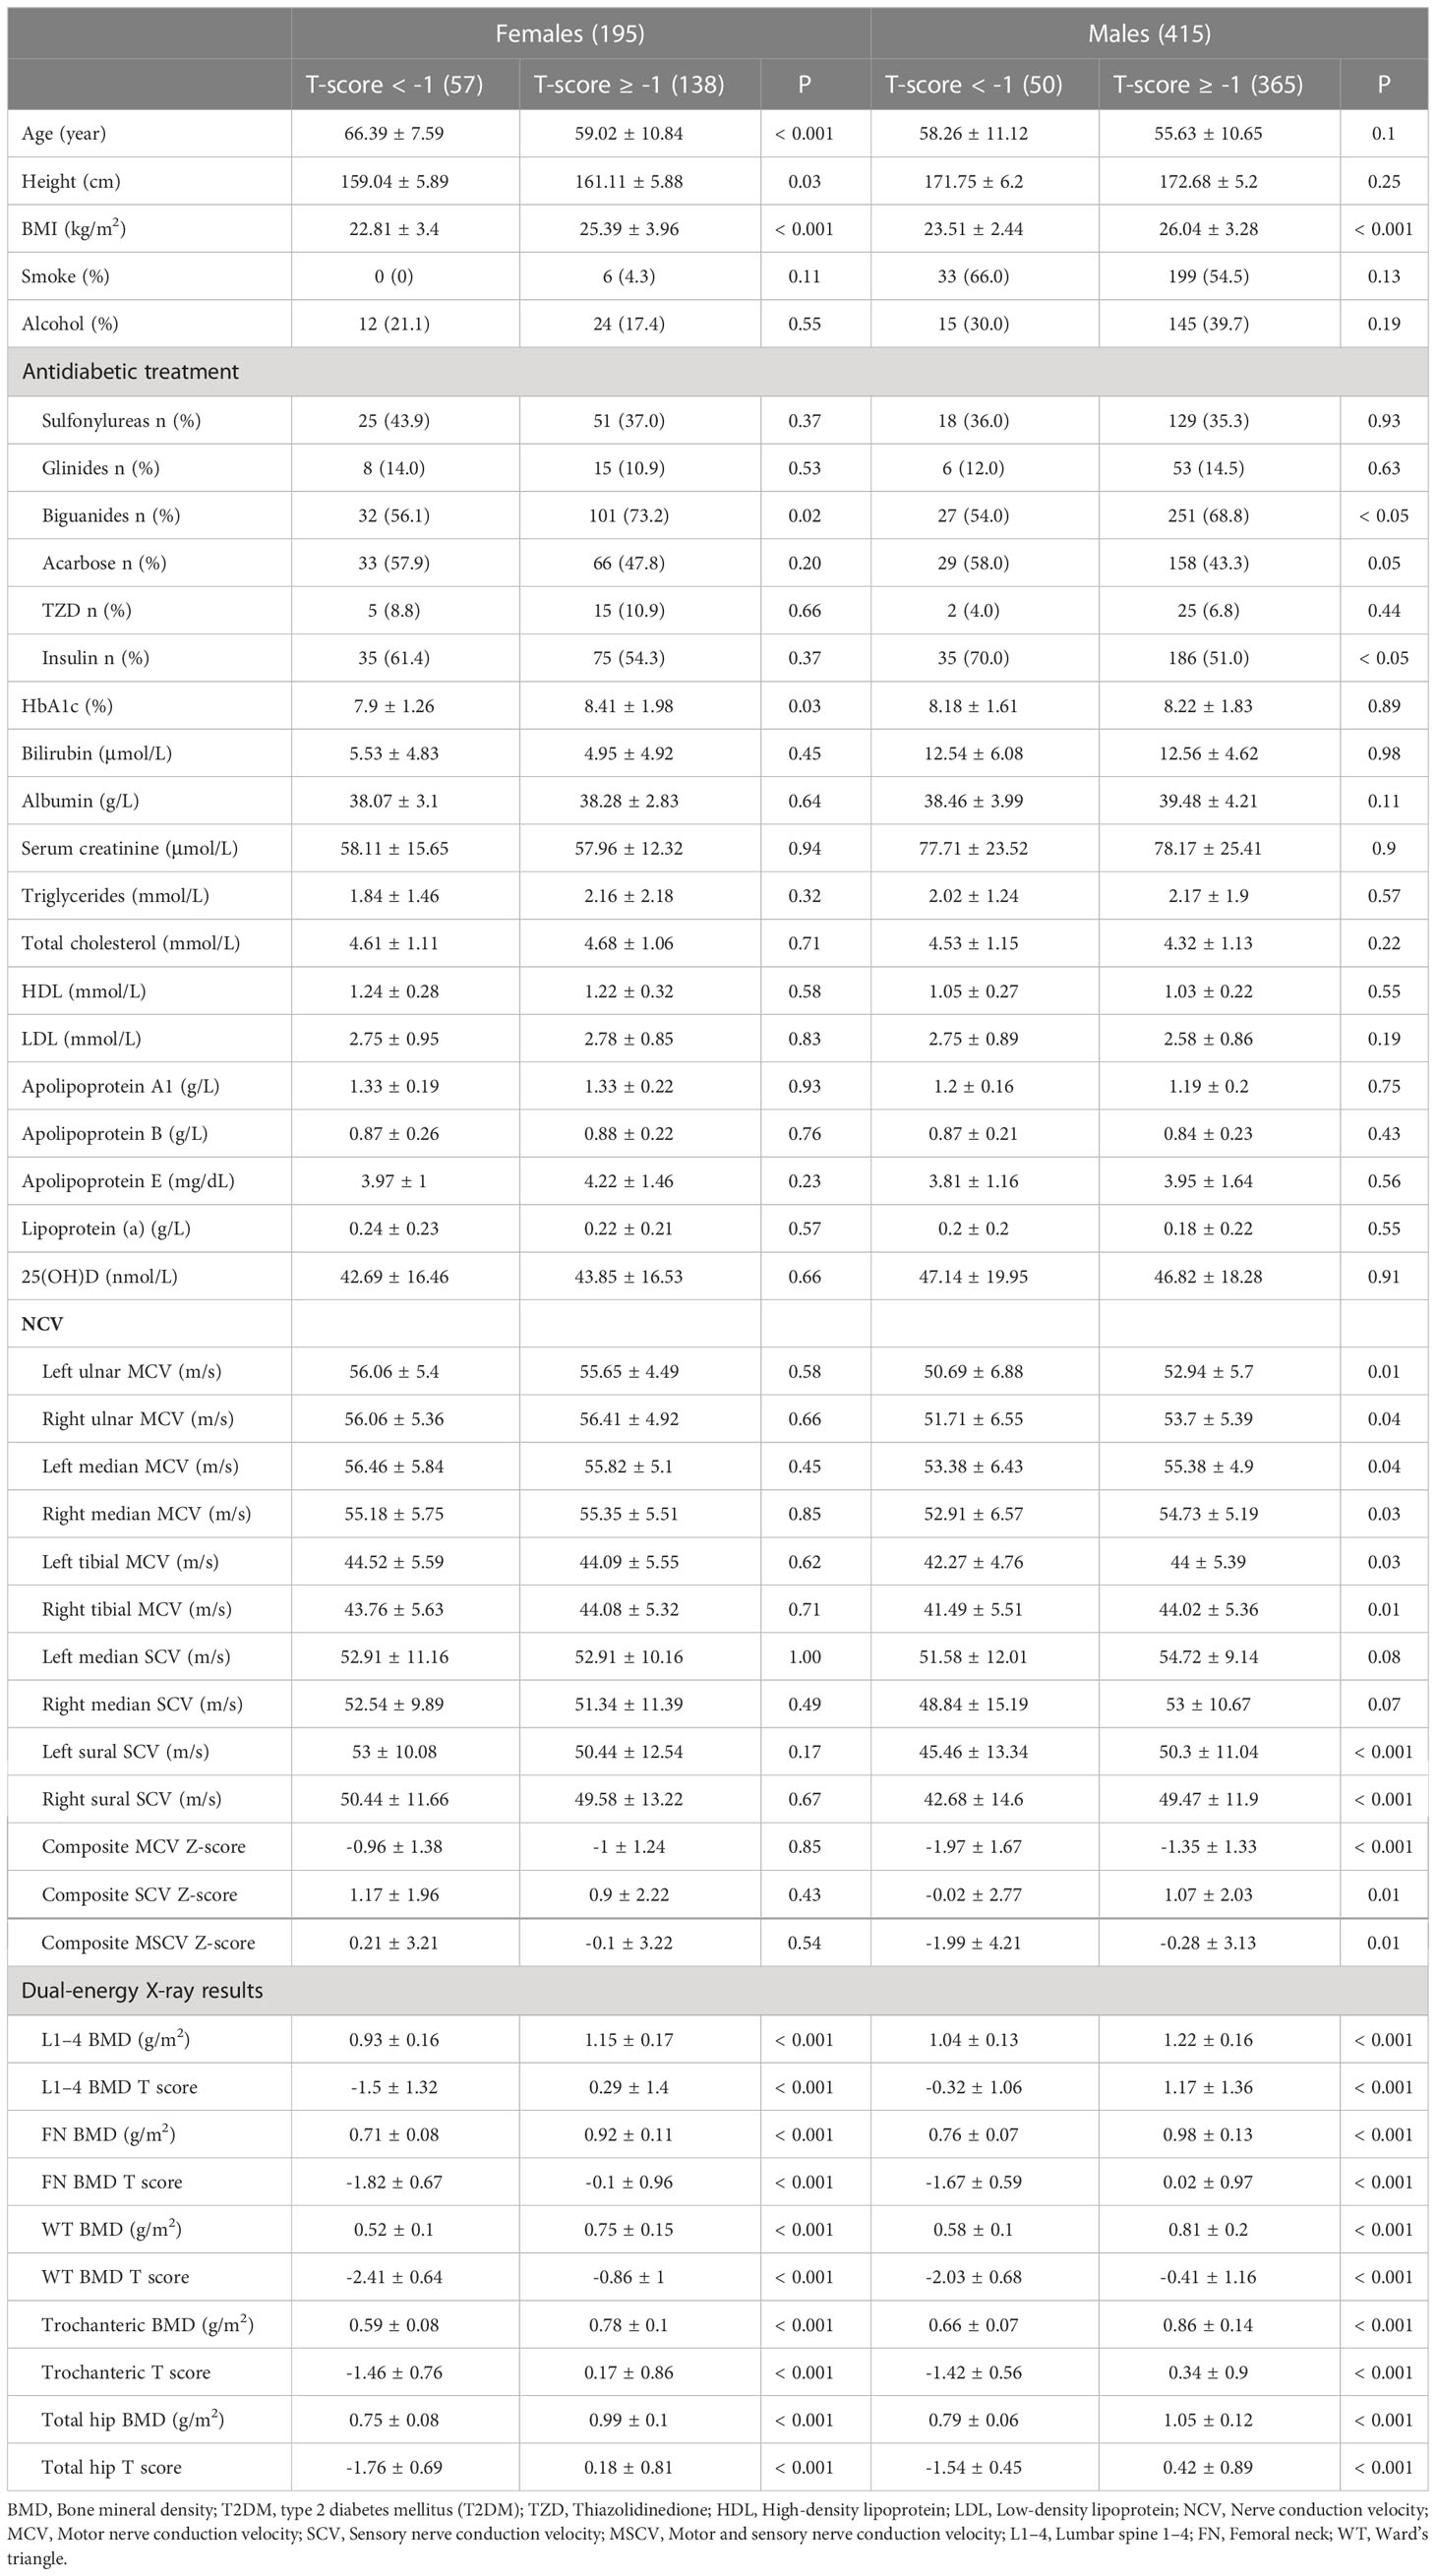

BMD T Scores At Baseline Download Table